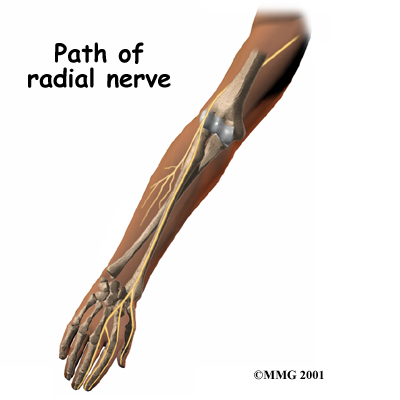

The radial nerve starts at the side of the neck, where the individual . The nerve roots exit through small openings between the vertebrae. These openings are called neural foramina.

The nerve roots join together to form three main nerves that travel down the arm to the hand. One of these nerves is the . The nerve passes down the back of the upper arm. It then spirals outward and crosses the outside (the lateral part) of the elbow before it winds its way down the forearm and hand.

On the lateral part of the elbow, the radial nerve enters a tunnel formed by muscles and bone. This is called the .

Passing through the radial tunnel, the radial nerve runs below the . The supinator muscle lets you twist your right hand clockwise. This is the motion of using a screwdriver to tighten a screw.

After the radial nerve passes under the supinator muscle, it branches out and attaches to the muscles on the back of the forearm.